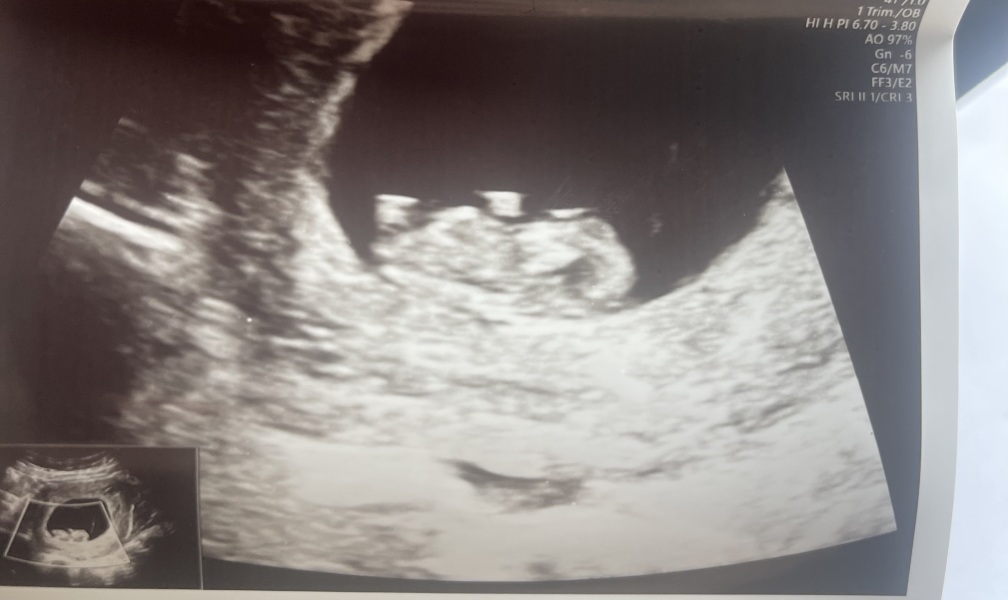

Hi everyone! We had our scan yesterday after a miscarriage in March, we are 9 weeks 3 days with a heartbeat of 171! Everything seems to be great, i’ve read a few posts about the nub theory and just wanted to see everyone’s thoughts? We are over the moon with this pregnancy and will be extremely happy whether it’s a boy or girl, i’m just curious! Thank you 😊xx